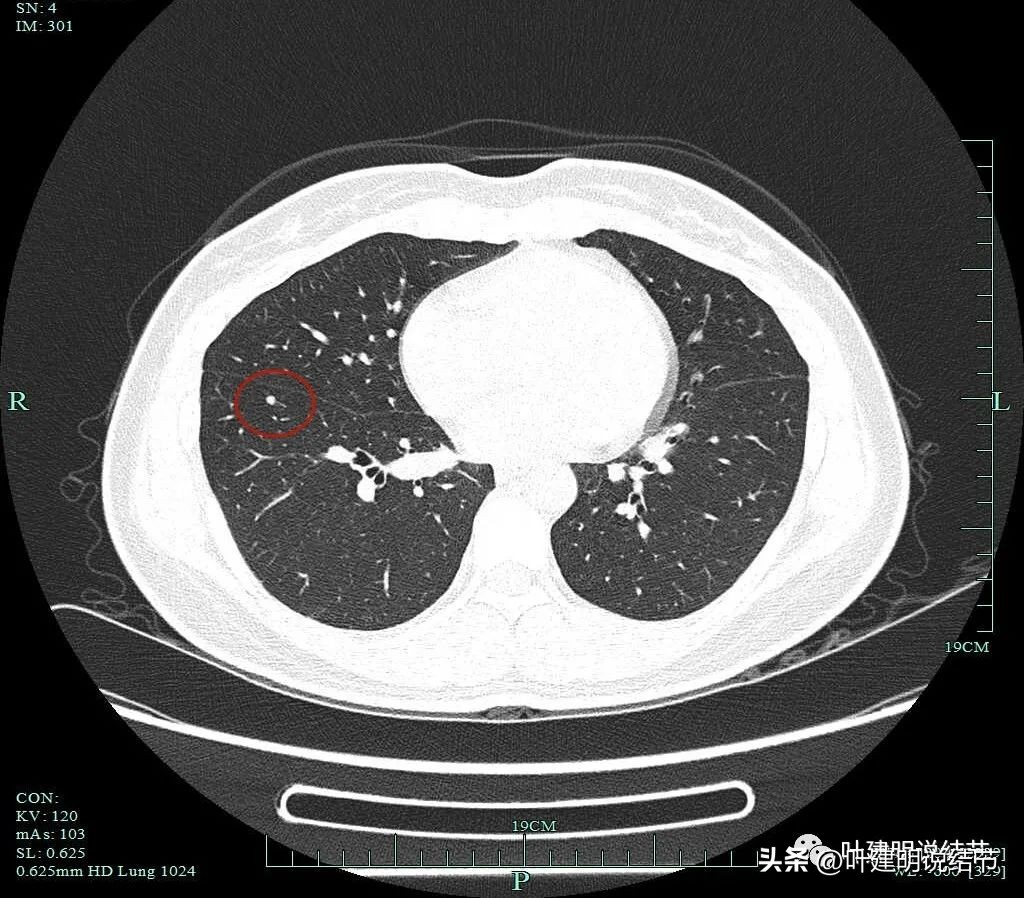

非薄层图像:

病灶1:右上叶淡磨玻璃结节,边缘较糊,似有微小血管走向病灶。

病灶2:右上叶混合磨玻璃结节,边缘毛糙,中间有空泡征,邻近有微小血管走向病灶。

病灶3:右下叶近叶裂处微小磨玻璃结节,偏长条状,有微血管进入。